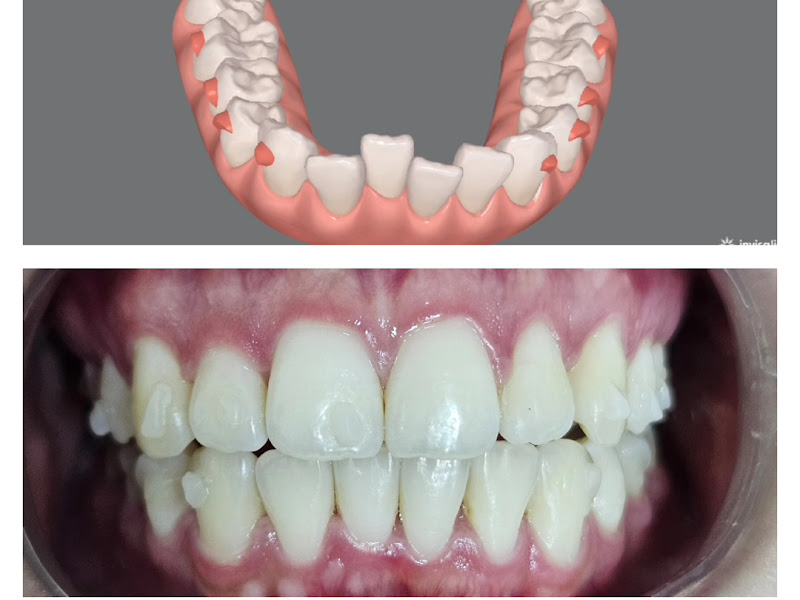

Fotos